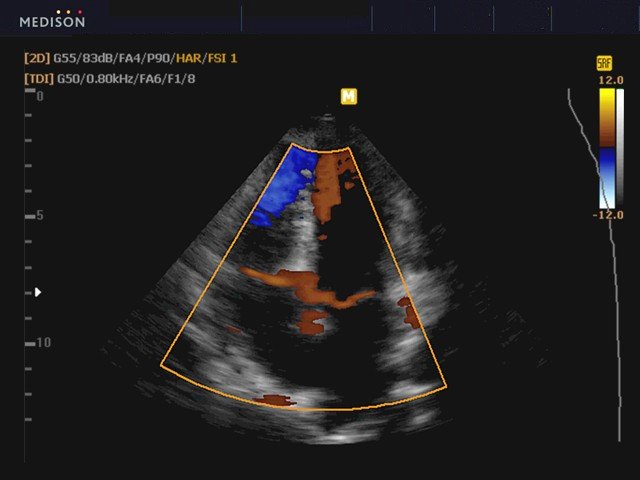

Сердце, тканевый допплер